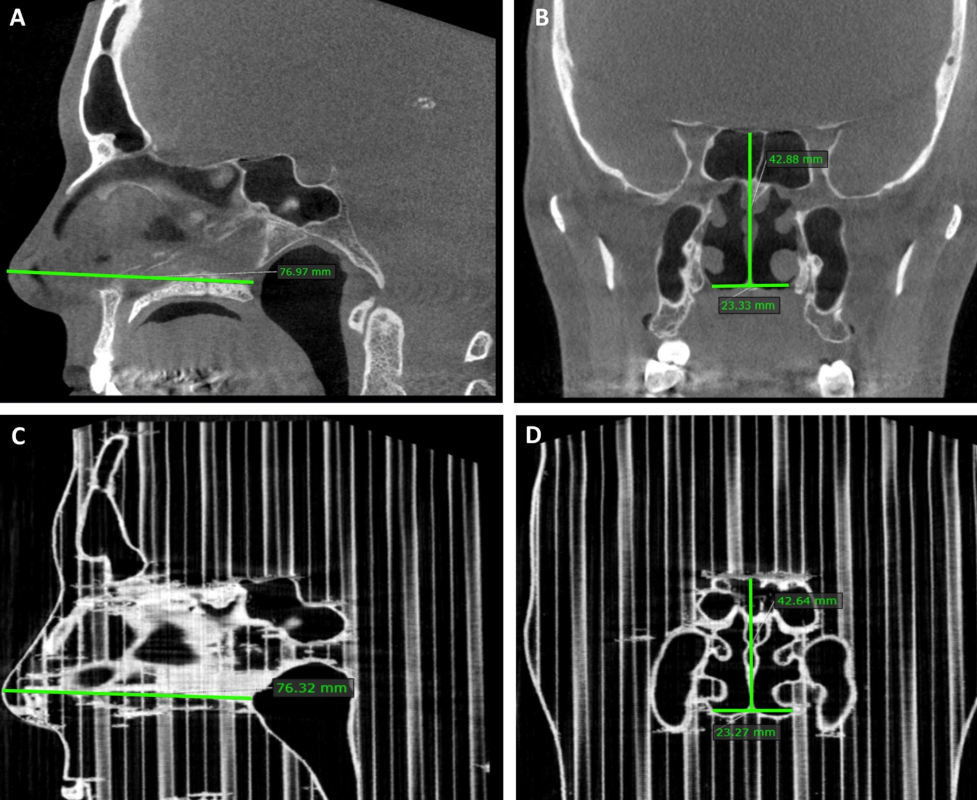

Measure the patient and the corresponding PLA model. The picture comes from the University of Tampere.

The team first performed cone-beam computed tomography (CBCT) scans on five adult patients with chronic nasal congestion. CBCT was chosen because of its relatively low radiation dose compared to conventional CT scans. Use MATLAB to convert the scanned data into a 3D printable format, and then use Slic3r to prepare and slice it. In order to maintain dimensional accuracy where possible, without supporting, all printing is done on Lulzbot Taz 4 with PLA 3D printingFinished on board.

In order to accurately compare the print with the patient’s nose, a CBCT scan was performed on all parts of the PLA.From the perspective of the maxillary sinus volume of the two scan groups, although it is considered to be very close to the actual value range,3D printingThe parts deviate slightly by 1.05 cubic millimeters.